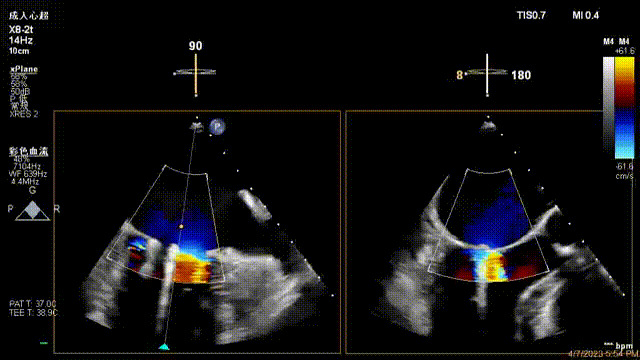

接受治療的是一例器質性重度二尖瓣反流(DMR)患者,主訴“反復活動后胸悶,氣促3年余”。術前超聲顯示,雙房增大,二尖瓣脫垂伴重度反流,輕度三尖瓣反流,輕度肺高壓,升主動脈增寬。手術經股靜脈-房間隔入路,采用全身麻醉插管,在TEE和DSA引導下完成房間隔穿刺。置入JensClip瓣膜夾系統后,在左房調整瓣膜夾的位置和軸向,后進入左室,在TEE引導下捕捉二尖瓣前后瓣葉,并關閉瓣膜夾。經TEE反復確認手術效果后最終鎖定并釋放瓣膜夾。術后即刻超聲顯示瓣膜夾位置穩定,功能良好,術前二尖瓣反流4+,術后0反流,肺靜脈逆流和左房壓都顯著好轉,手術圓滿成功(以上數據都來源于醫院的臨床記錄)。術后患者狀態良好,目前已安排出院。

術后超聲顯示二尖瓣反流消失,瓣膜夾穩定